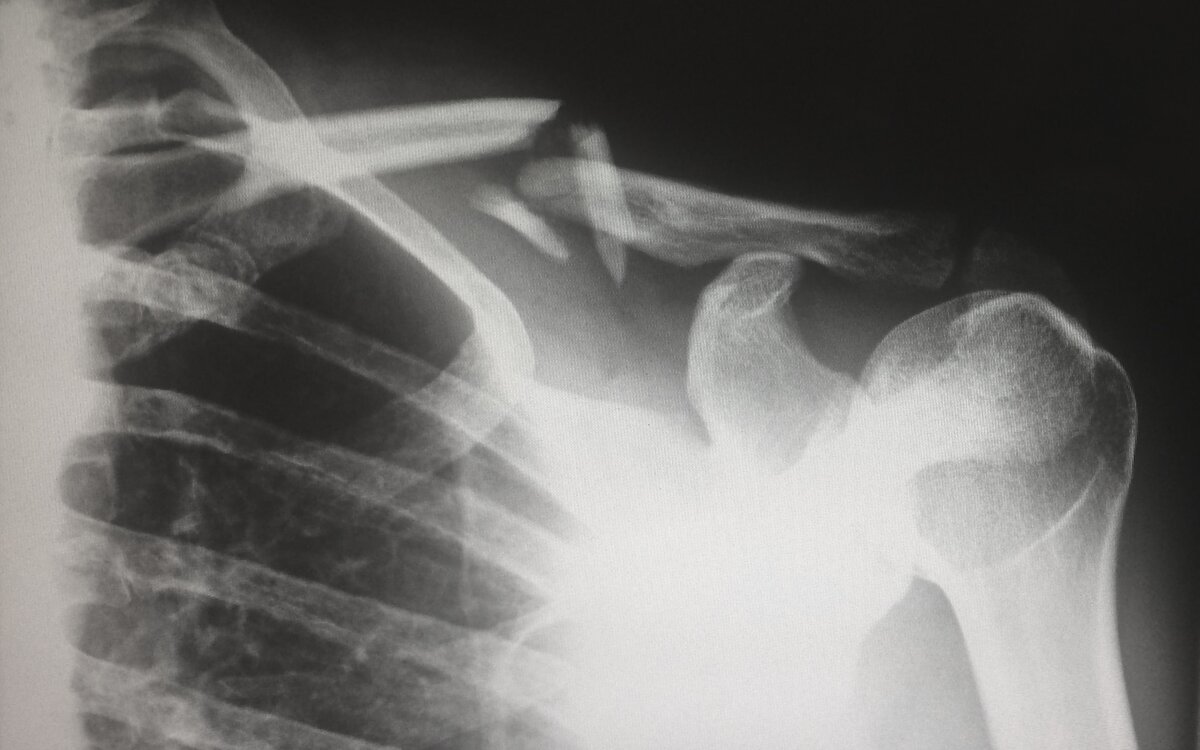

Остеопороз в медицине определяется как нарушение микроструктуры кости, приводящее к потере её плотности и прочности. Это состояние опасно тем, что при минимальной травмирующей силе – падении с высоты собственного роста или неловком движении – может произойти перелом. Для людей, страдающих этим заболеванием, чаще всего характерны травмы костей предплечья, тел позвонков, но в целом перелом может произойти в любом месте. Причин развития заболевания может быть множество: некоторые лекарственные препараты, генетическая предрасположенность, недостаточность питания, осложнения от первоначального диагноза, вредные привычки. Выявить остеопороз на ранних стадиях формирования невозможно, чаще всего болезнь распознаётся только после перелома. Но есть возможность спрогнозировать заболевание: нужно следить за изменениями роста, особенно после 40 лет. Так, например, уменьшение роста на 4-5 см – повод обратиться к врачу. Стоит обращать внимание и на беспричинные боли в ногах или спине, на признаки нед

Для людей, страдающих этим заболеванием, чаще всего характерны травмы костей предплечья, тел позвонков, но в целом перелом может произойти в любом месте.